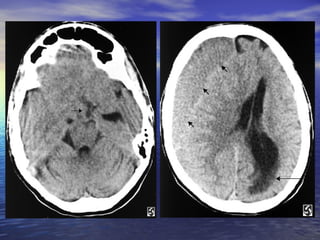

• #17 Slide #16 Subdural Hematoma Case: A 26 yo female presents to her family practice physician complaining of a headache that has persisted for over one month and sporadic blurry vision that has worsened over the last week. The headache is only slightly relieved with Ibuprofen and is worse when doing strenuous activity. The blurry vision comes and goes and can last minutes to hours when it is present. The neurologic and physical exams are normal except for some slight papilledema. The patient was then sent for a CT exam, the results of which are shown here. Diagnosis: Subdural Hematoma

• #18 Slide #17 Axial CT images of the brain show a large isodense right-sided subdural hematoma ( short arrows ) extending from the high convexities to the low frontal lobe. It is producing extensive right to left midline shift with subfalcine ( arrow )

• #19 Slide #18 and right uncal (arrow) herniation. There is trapping of the ventricles and left temporal horn with acute ependymal cerebrospinal fluid seepage, predominantly in the left periatrial and occipital regions (long arrow).

• #20 Slide #19 Subdural Hematoma